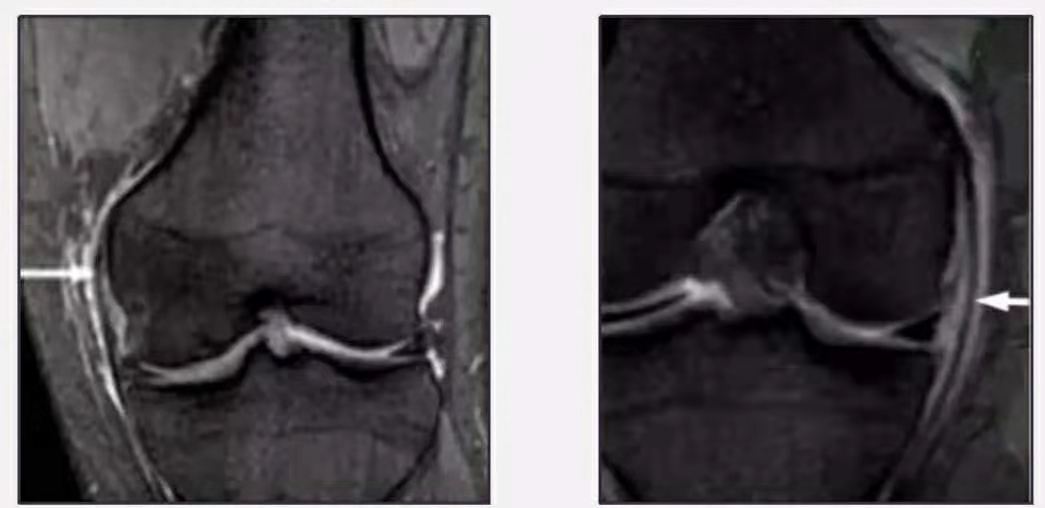

MRI检查是发现内侧副韧带损伤的首选影像学检查方法,并能判断其损伤分级。

I度:韧带内侧(浅层)高信号,病变不明显;

图4.内侧副韧带I度损伤(图片来源于网络)

II度:韧带内侧(浅层)高信号,伴水肿或韧带部分中断;

图5.内侧副韧带II度损伤(图片来源于网络)